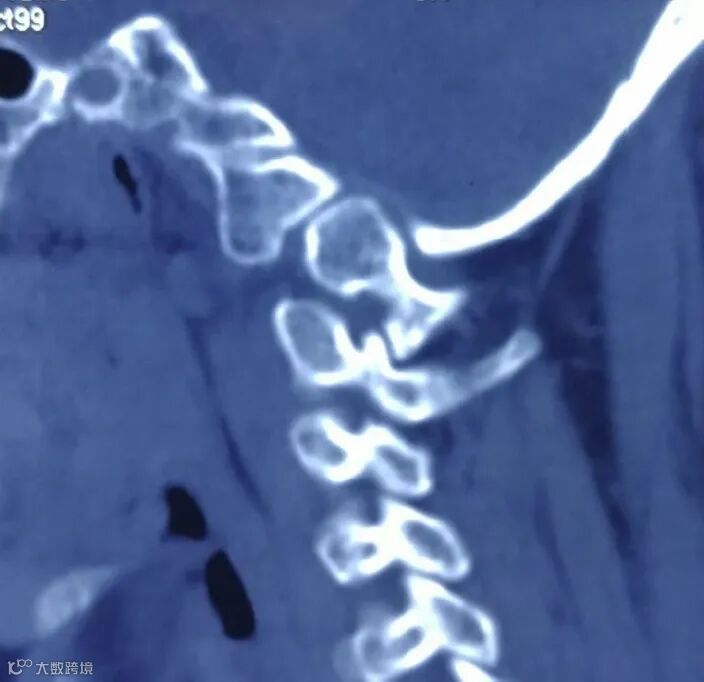

通过后路关节间撑开可以有效松解寰枢椎前方张力带,使寰枢椎侧方关节纵向分离,复位颅底凹陷和寰枢椎脱位。在寰枢椎关节间隙植入高度适宜的关节间融合器,通过融合器的支撑使寰枢椎关节纵向分离后保持稳定。而后以关节间融合器为支点,通过后路内固定系统进行悬臂操作,可以进一步复位寰枢椎水平脱位(图2)。PFDF技术大幅度提高了寰枢椎脱位后路手术的复位率,简化了寰枢椎脱位复位手术技术,降低了手术难度,提高了手术的安全性[6, 7]。

通过在寰枢椎关节间进行撑开,达到松解前方张力带,使寰枢椎关节纵行分离,解除寰枢椎关节绞锁。然后在纵行分离的关节间隙内植入融合器,使关节间隙保持稳定(图3)。